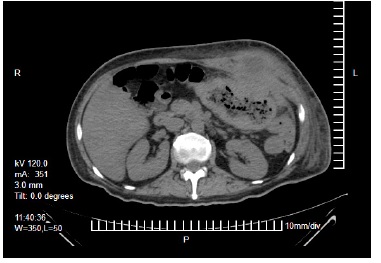

Laboratorios a su ingreso: hemoglobina 9,3 g/dL, hematocrito 29,6 %, plaquetas 574 x 109/L y albumina 1,6 g/dL, resto dentro de parámetros normales. Se realizó una tomografía abdominal que reportó un tumor dependiente del colon transverso con invasión a pared abdominal y formación de absceso (Figura 1, 2 y 3). Con el paciente en estado séptico, se decide el drenaje y la exploración quirúrgica previa estabilización.

La utilidad de la colonoscopia y la biopsia por este medio, han sido las herramientas de tamizaje y diagnóstico temprano [13-15], sin embargo, esta herramienta tiene sus limitaciones al estar confinada a la luz intestinal, así como un riesgo de error en la toma de biopsia en caso de un tumor heterogéneo. En los casos de absceso de pared abdominal, independientemente de su origen, la tomografía juega un papel crucial en el diagnóstico [10,16].